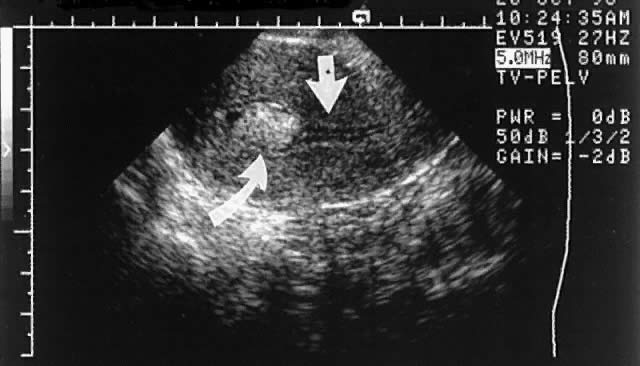

It appears that sonohysterograms are not more sensitive for the detection of submucous leiomyomas than transvaginal scans without infusion. However, this is deceptive, because the degree of myometrial involvement frequently cannot be accurately mapped without saline infusion. This problem can lead to inappropriate case selection (Figs. 8 and 9).

Fig. 9. A. A centrally located leiomyoma is identified, but the endometrial stripe is poorly seen. B. After saline infusion, a submucous leiomyoma with more than 50% penetration into the myometrium (category T-II) is seen.